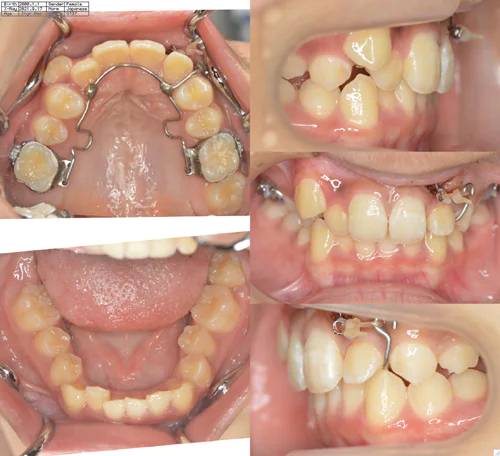

case.6(渡邊様)

治療前 治療中 治療後

治療開始の年齢 10歳

治療名 上顎右側1,2番埋伏歯の牽引及び配列

治療内容 埋伏歯の牽引及び乳歯の生え変わり後全顎矯正

費用 770,000円

治療期間 5年2カ月